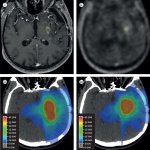

Mit Hightech-Mikroskopie zu neuen Erkenntnissen zum Glioblastom: Forschende konnten jetzt zeigen, dass Interaktionen zwischen Tumorzellen und Mikroglia eine wichtige Rolle bei der Ausbreitung spielen.